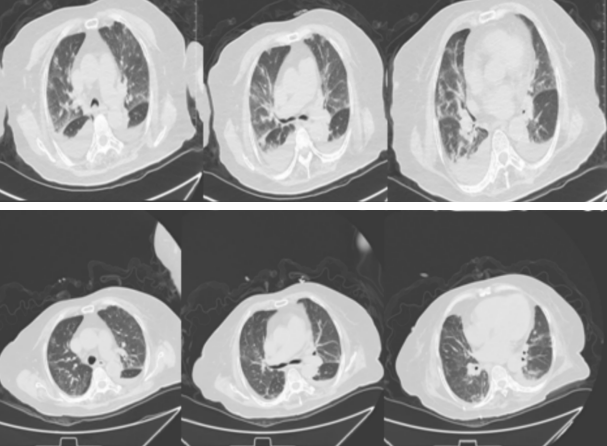

事情回到 1月12日,吳奶奶突發(fā)胸悶,呼吸困難,加重伴發(fā)熱,15日急診CT檢查結(jié)果顯示雙肺感染,情況十分危急。隨后從急診轉(zhuǎn)入感染內(nèi)科二區(qū)進(jìn)行救治,入院時(shí)血氧低,呼吸衰竭狀態(tài),一度生命垂危。

在時(shí)任感染二區(qū)科主任的梁志朋副主任醫(yī)師的帶領(lǐng)下,立即予無(wú)創(chuàng)呼吸機(jī)輔助呼吸治療,同時(shí)給予抗感染、祛痰、平喘、抗心衰、護(hù)腎、監(jiān)測(cè)生命體征、控制血糖、血壓等處理,在感染二區(qū)住院時(shí)吳奶奶肺炎、呼吸衰竭明顯癥狀改善、病灶吸收。